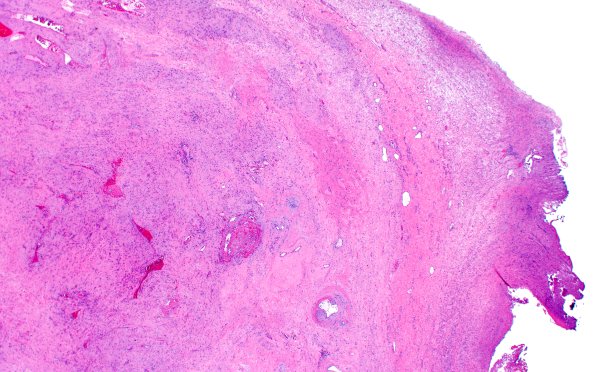

32B2 Schwannoma (Case 32) H&E 2X

Low magnification image show the originating nerve at the margins of the hypocellular neoplasm. (H&E)